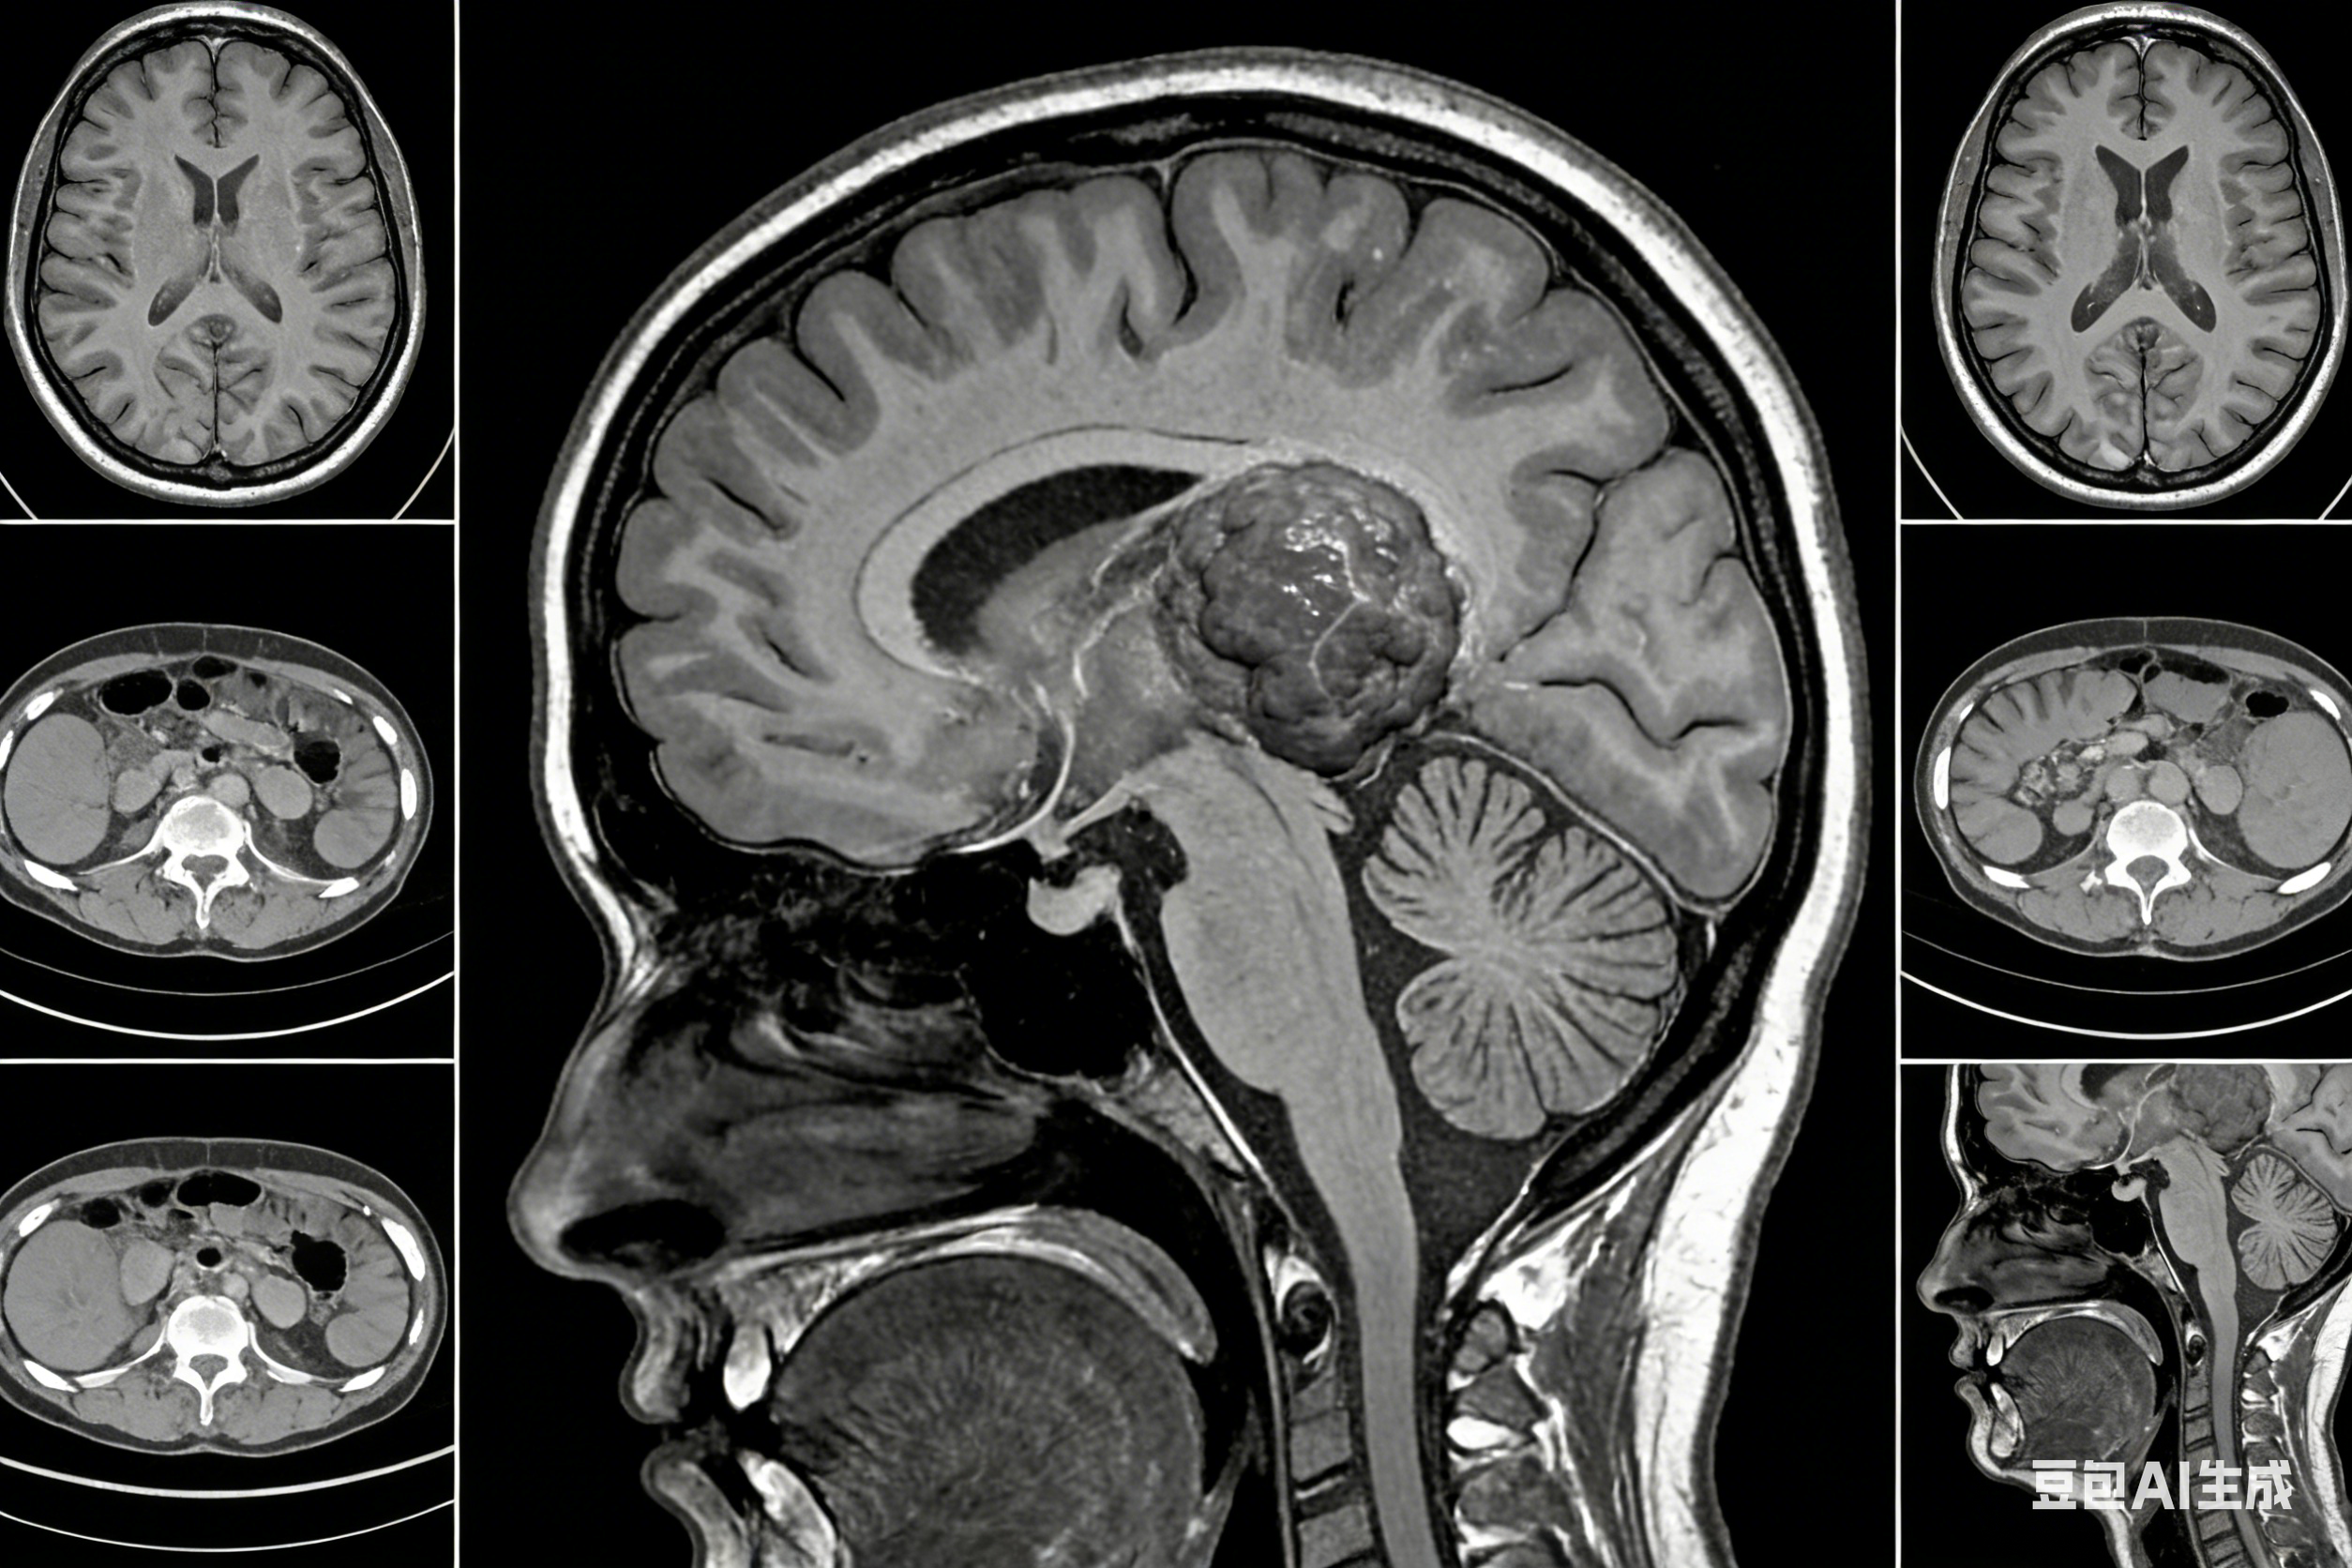

天津市环湖医院眩晕中心成立于2021年12月3日,该中心采用以耳鼻咽喉头颈外科、神经内科联合诊疗为主,急诊科、康复科、骨科、心理科、神经外科、内科、眼科等共同参与的多学科诊疗模式。通过多学科融合,实现眩晕疾病的预防、检查、诊断、治疗、康复和随访为一体的高质量、高效率的一站式服务体系,实现了眩晕疾病的中心化诊疗模式,发挥了我院眩晕联合诊疗的专科特色,推动我市眩晕诊疗水平实现跨越式发展。天津市环湖医院眩晕中心诊疗团队由眩晕相关学科的数十名主任及医生组成。下设:眩晕专病门诊、眩晕急诊、眩晕MDT专家诊疗高端门诊、眩晕病房、前庭康复训练中心、利用信息化手段打造的眩晕智慧诊疗中心、眩晕检查室、眩晕实验室、眩晕专项科研管理中心、眩晕患者随访中心,致力于眩晕疾病的个体化和精准化治疗。眩晕专业组由眩晕急诊、眩晕专病门诊及眩晕病房团队(医生、技师)组成,在眩晕中心主任、副主任的领导下开展眩晕MDT多学科合作诊疗工作,眩晕中心秘书负责眩晕中心的日常管理及组织协调工作,并定期向眩晕中心领导进行工作汇报。眩晕急诊由神经内科和耳鼻咽喉头颈外科医生共同负责接诊急诊眩晕病人,为急难险重的眩晕患者开启急诊眩晕检查绿色通道,在6小时之内完成头CT及MRI、MRA检查,在2小时之内完成前庭功能及听觉功能筛查,尽早鉴别出有致死致残风险的中枢性眩晕患者,给予急救处理及尽早安排至中枢性眩晕病房(神经内科七病区)住院治疗,筛查出良性阵发性位置性眩晕-耳石症、突发性耳聋伴眩晕、前庭神经炎及梅尼埃病急性发作的周围性眩晕患者给予急诊对症治疗,并尽早安排患者至周围性眩晕病房(眼耳鼻咽喉头颈外科中心)住院治疗。眩晕门诊由耳鼻咽喉头颈外科、神经内科、神经康复科主任医师、副主任医师及主治医师共同应诊,合作开展中枢性眩晕及周围性眩晕的影像学、超声学检查、由专业技师进行前庭功能、听觉功能相关检查、晕厥的脑电监测及直立倾斜试验,设立耳石复位检查室进行良性阵发性位置性眩晕的变位试验检查、手工及机器耳石复位治疗,与康复医学科合作进行眩晕恢复期患者的手工及虚拟现实技术VR前庭康复训练治疗,并进行眩晕患者的随访复查,预防宣教及长期慢病管理。眩晕病房由中枢性眩晕病房(设在神经内科七病区)和周围性眩晕病房(设在眼耳鼻咽喉头颈外科中心)组成,在眩晕中心主任和两位病区科主任的统一领导下开展眩晕住院患者的MDT多学科联合诊疗,两个病区的眩晕学组由眩晕专业的主任医师、副主任医师、主治医师和住院医师组成,定期进行三级查房,眩晕疑难病例讨论,两个病区可以进行会诊及相互转诊,诊疗范围涉及眩晕的检查、诊断、治疗、康复训练、随访复查及科普教育,实现眩晕专病的一体化诊疗,实现中枢性眩晕及周围性眩晕的诊疗全覆盖的一站式服务。